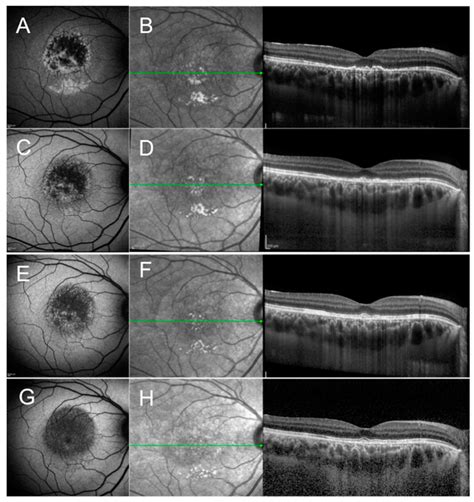

To confirm a diagnosis of Csr Eye Disorder, an ophthalmologist will perform a comprehensive eye examination. Specialized imaging tools are used to visualize the retina and the fluid accumulation beneath it.

Optical Coherence Tomography (OCT) Provides high-resolution cross-sectional images of the retina to measure fluid accumulation.

Fundus Autofluorescence Used to assess the health of the retinal pigment epithelium.